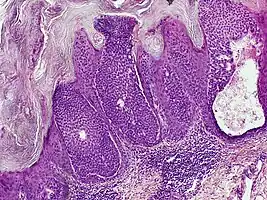

Histology

They are described as < 1 to 2 cm, pink/red shiny, exophytic lesions that can be pigmented and are clinically very similar to pyogenic granulomas.[3] Histologically, the cells as PAS-positive and clearly surrounded by normal keratinocytes. These tumors are surgically excised usually without complication or recurrence, although malignant porocarcinomas can recur and metastasize to local lymph nodes.[5]

Dermoscopy and histopathology of eccrine poroma: (A) Clinical presentation of a nonpigmented eccrine poroma sensu stricto as a pink nodule located on the foot (B,C) Dermoscopy shows milky red areas (light blue arrow), milky red globules (dark blue triangle), and dotted vessels (black arrow) (original magnifications ×20 and ×40, respectively). (D,E) Histopathologically, the neoplasm consists of poroid and cuticular cells and tubular structures that are continuous with the epidermis (H&E stain, original magnifications ×10 and ×40, respectively).[6]